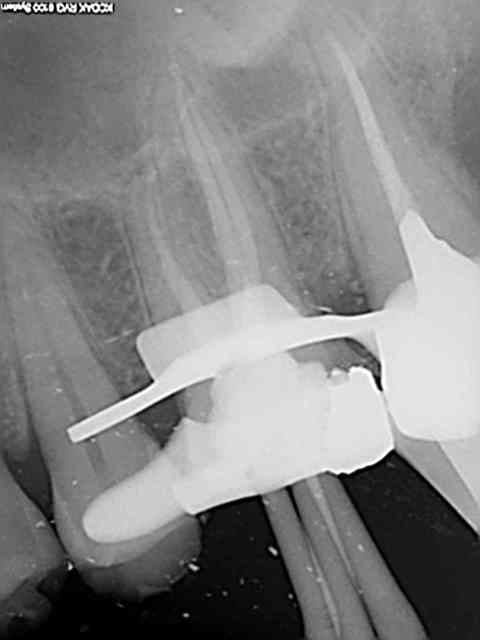

26, 60 mn endo molaire dont 30 pour trouver le canal DV (chambre calcifiée). J'ai failli jeter l'éponge mais le sx a fini par s'engager. Grosse frayeur toutefois avec le s1 sur endomaster car il a bipé d'ès son entrée dans le canal, mais c'était du à un excès d'irrigant. Ouf !

36, 30 mn endo molaire, vitesse de croisière retrouvée !))))